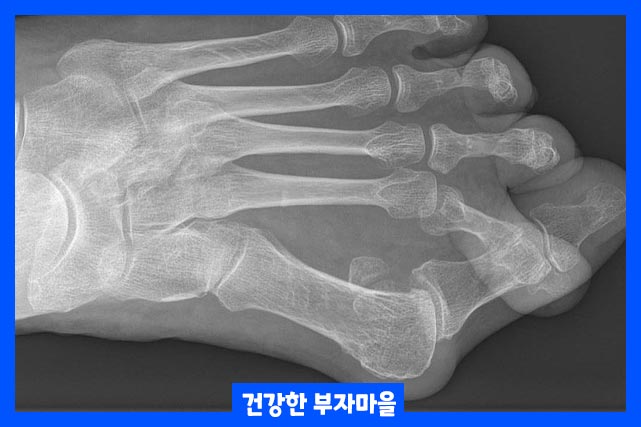

| 요약 : 엄지 발가락 관절이 두번째 발가락 쪽으로 휘고 엄지발가락과 관절을 이루는 중족골은 반대로 안쪽으로 치우치는 증상을 말합니다. |

건막류라고도 알려진 무지외반증(Hallux valgus)은 가장 흔하게 찾아볼 수 있는 앞발 기형 증상입니다. 근위 지골이 측면으로 휘고, 첫 번째 중족골 머리가 내측으로 휘어 있습니다.